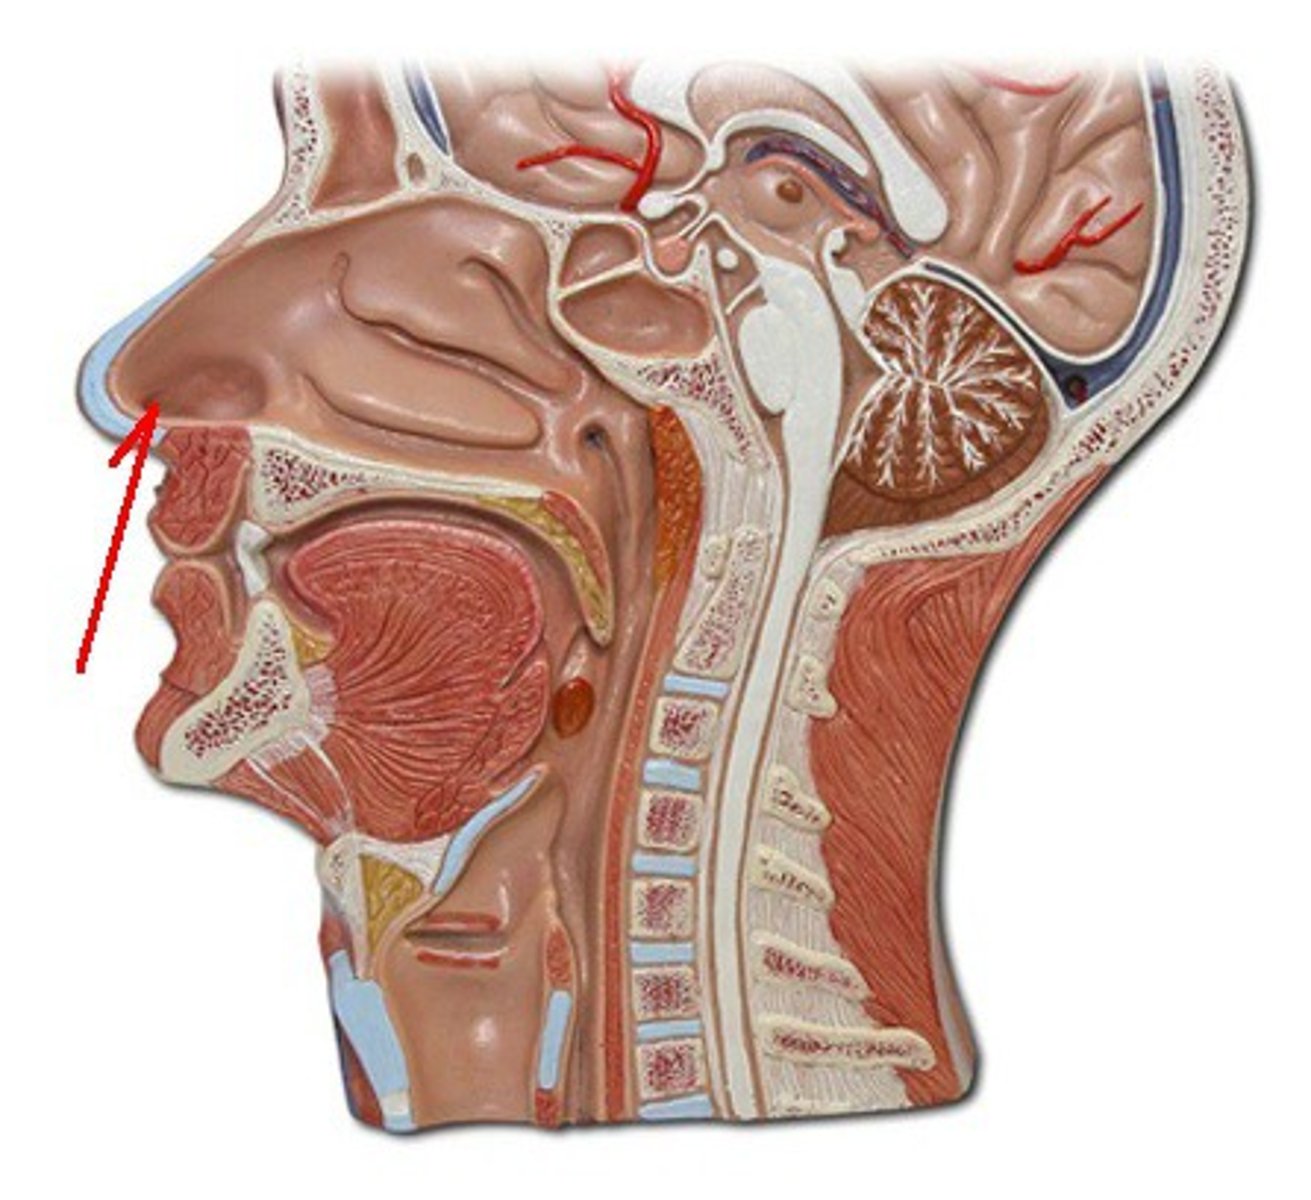

external nares

knowt flashcard image

nasal vestibule

nasal septum

nasal cavity

superior, middle, and inferior nasal conchae (or turbinates)